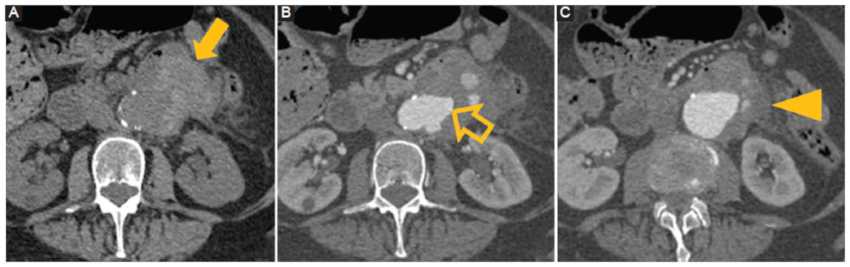

Aneurisma focal y sacular de etiología infecciosa, más frecuentemente bacteriana, de rápido crecimiento que se desarrolla de manera excéntrica, de localización a veces inhabitual con cambios inflamatorios adyacentes. Los microorganismos más frecuentes asociados a esta patología son Staphylococcus y Streptococcus spp., seguidos de Salmonella. Si este proceso infeccioso compromete a la aorta (Fig. 1) se puede extender hacia el cuerpo vertebral o el músculo psoas adyacentes1.

Aneurisma micótico (infeccioso). Hombre de 75 años con antecedentes de hipertensión y diabetes. Fiebre y dolor abdominal de dos semanas de evolución. TC con contraste en cortes axiales. A: fase sin contraste. B y C: fase arterial. Se observa un tejido con densidad de partes blandas periaórtico (flecha) adyacente a una pequeña saliente de perfil (flecha hueca) en la pared lateral izquierda de la aorta con inflamación de los tejidos blandos periaórticos (punta de flecha).